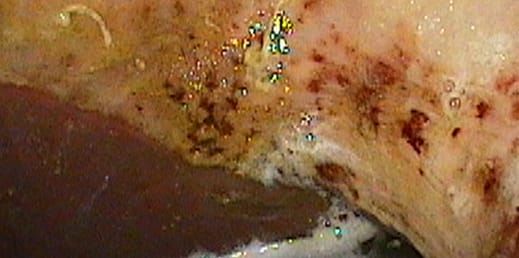

Grade 3:

Stomach has large single or multiple ulcers.

Grade 4:

Stomach has extensive ulcers, often with areas of deep ulceration.